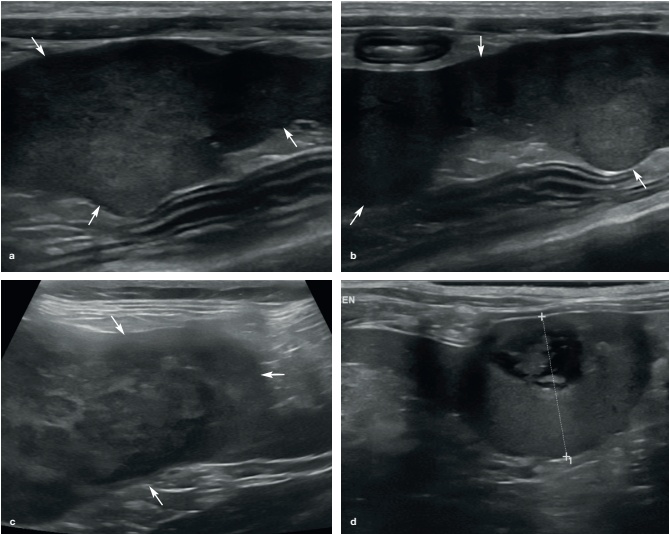

고양이에서 가장 흔한 종양은 mast cell tumor(비만세포종)와 lymphoma입니다.4)

림포마 환자에서 가장 흔한 소인은 비장의 비대입니다. 비장의 실질은 편만한 저에코성과 얼룩덜룩한 형태의 병소를 보이며, 적은 여러 개의 저에코성 병소부터 독립적인 저에코성의 종괴로 나타납니다. 어떤 경우는 비장의 종괴 혹은 비장의 비대가 없이 실질의 에코가 떨어져 보이기도 합니다. 그리고 복수와 복강내 림프절 크기 종대, 간의 이상증이 같이 나타납니다.

a) 거세 수컷 고양이에서 나타난 lymphoma. 1. 비장, 2. 비장림프절, 3. 소장분절, 비장은 저~중등도의 비장비대를 보이며, 실질은 저에코성의 병소를 나타내 보임.

b) 수컷 고양이에서 나타난 lymphoma. 1. 비장, 2. 간, 3. 담낭, 약간의 비장비대와 함께 실질에서 이질성을 보임.

c) 수컷 성묘에서의 나타난 lymphoma. 비장의 몸통에서 경계부위가 뚜렷하지 않은 한 개의 저에코성의 결절을 보임.

d) 6살 암컷 고양이에서 나타난 lymphoma. 실질의 이질적인 형태와 여러 개의 저에코성의 병소를 보임.